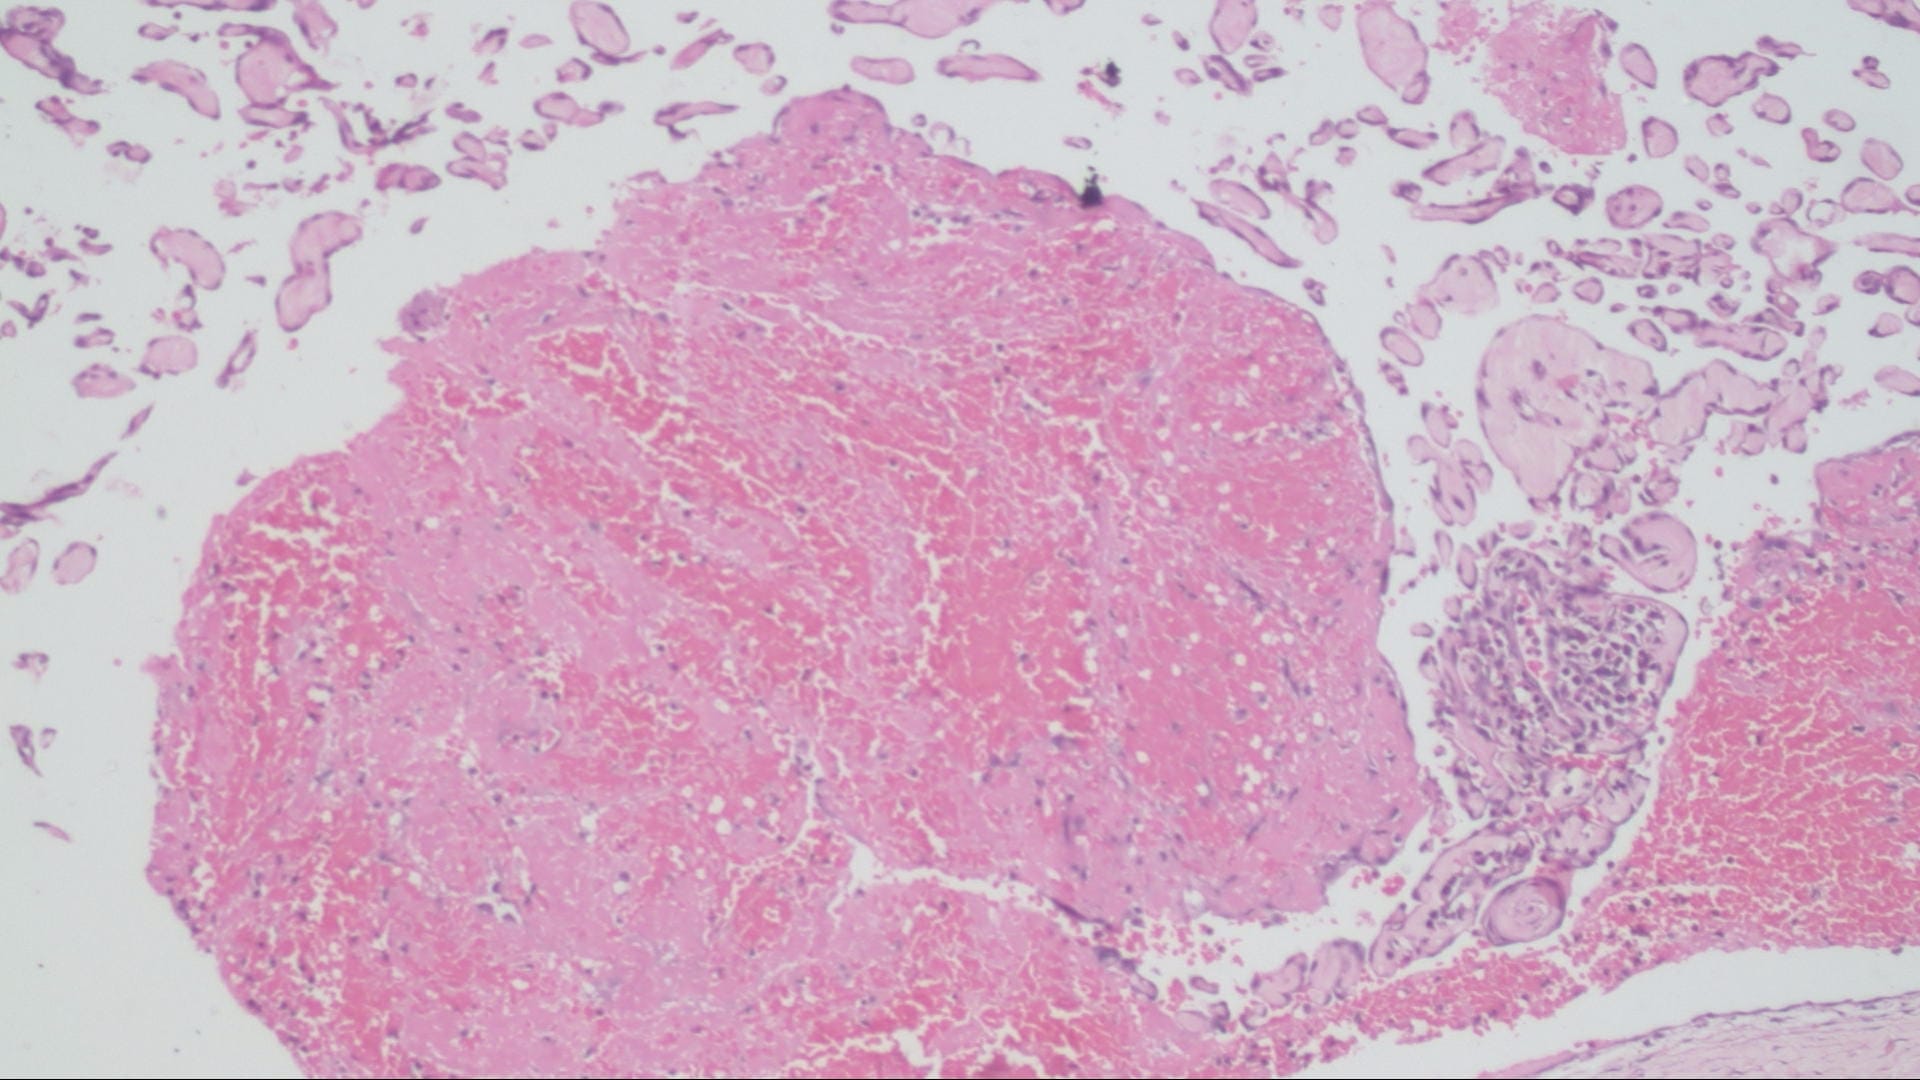

Organizing thrombi Histopathology.guru Thrombosed Hemorrhoids Pathology Outlines This is known as a protruding hemorrhoid. Internal hemorrhoids typically cause any combination of itching, bleeding, swelling, and prolapse; Have a brief scroll through the tissue to confirm the diagnosis of hemorrhoids (submucosal vessels with dilation, thick walls. Hemorrhoid may protrude through the anus outside the body, becoming irritated and painful. • acutely thrombosed external haemorrhoids are seen as purple,. Thrombosed Hemorrhoids Pathology Outlines.